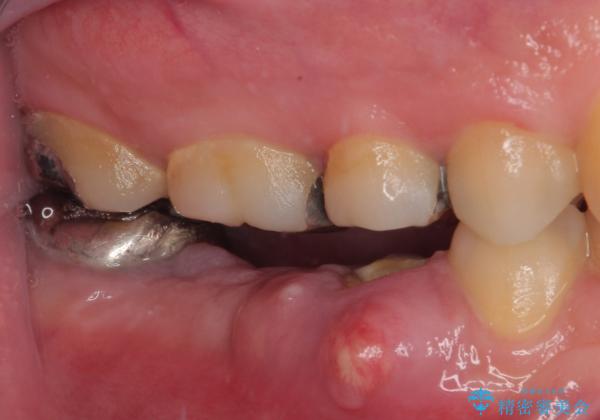

咬合力が非常に強い患者様であり、2歯欠損のブリッジ(しかも大臼歯は失活歯)は歯根破折のリスクが高すぎると判断し、抜歯部および欠損部に対して、インプラントによる補綴治療を行うこととしました。

抜歯即時埋入部と後方の欠損部は、即日荷重(インプラント埋入と同時に仮歯を装着すること)が可能な安定値が得られましたが、長い期間欠損した状態で過ごすと、欠損部に舌を押し当てる癖が発現してしまい、舌からの側方圧でインプラントが脱離するリスクが著しく高まってしまうため、即日荷重は行いませんでした。

おかげでインプラントは無事に生着し、僅か4ヶ月で治療を終えることができました。